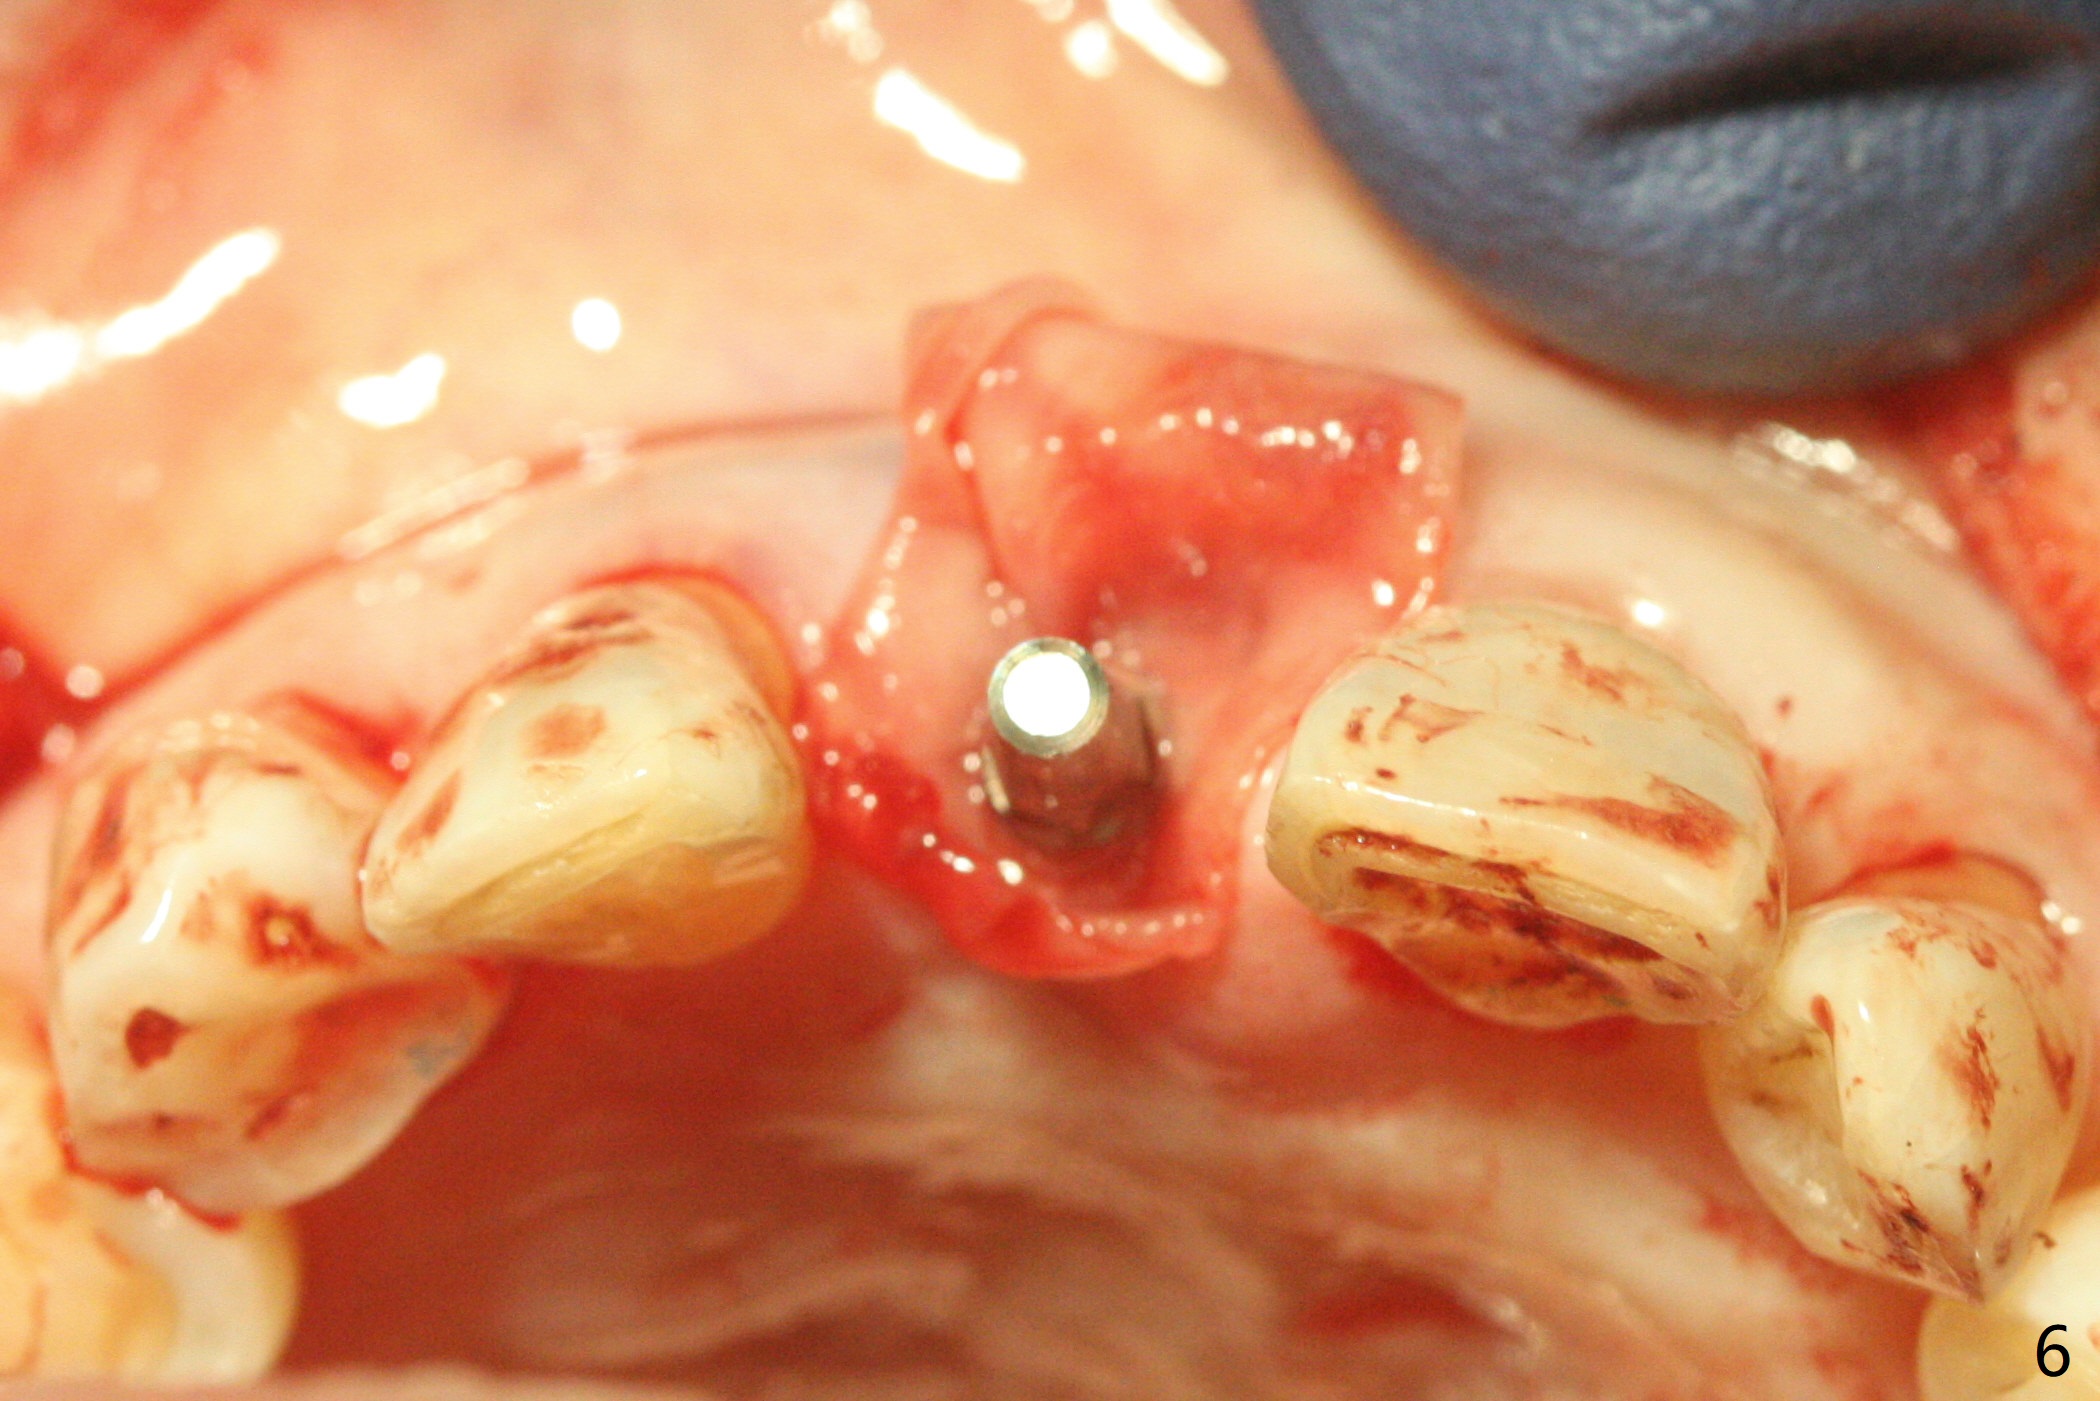

59岁女术前右下1,2切缘磨短后,右上1颊侧移位得到纠正(图一(咬合创伤))。拔牙后证实颊侧骨板缺失,钻洞始于腭侧(图二),当1.5毫米钻头感觉刚穿破鼻底时,置入2.5x14(4)毫米一段式植体,好像进入鼻腔,但是扭力<10Ncm(图三)。把一张PRF膜放入牙槽窝,一端紧贴颊侧牙龈腭侧,另一端放置颊侧牙龈颊侧(图四),然后开始用粘性骨粉(图五,七:*(100%皮质骨))充填颊侧间隙。后者填满时(图五:*),将外面一端PRF翻转覆盖牙槽窝开口,并插入基台固定(图六),最后插入龈下,用临时牙冠固定(图八(T),九(*:PRF))。术后九天牙龈退缩(图十:^),临时牙冠突出(*),后者龈缘和切缘进行调整,缩短(图十一,十二),少许骨粉暴露(图十二:>),十四天后牙龈往下生长,好像形成角化龈(图十三:*)。